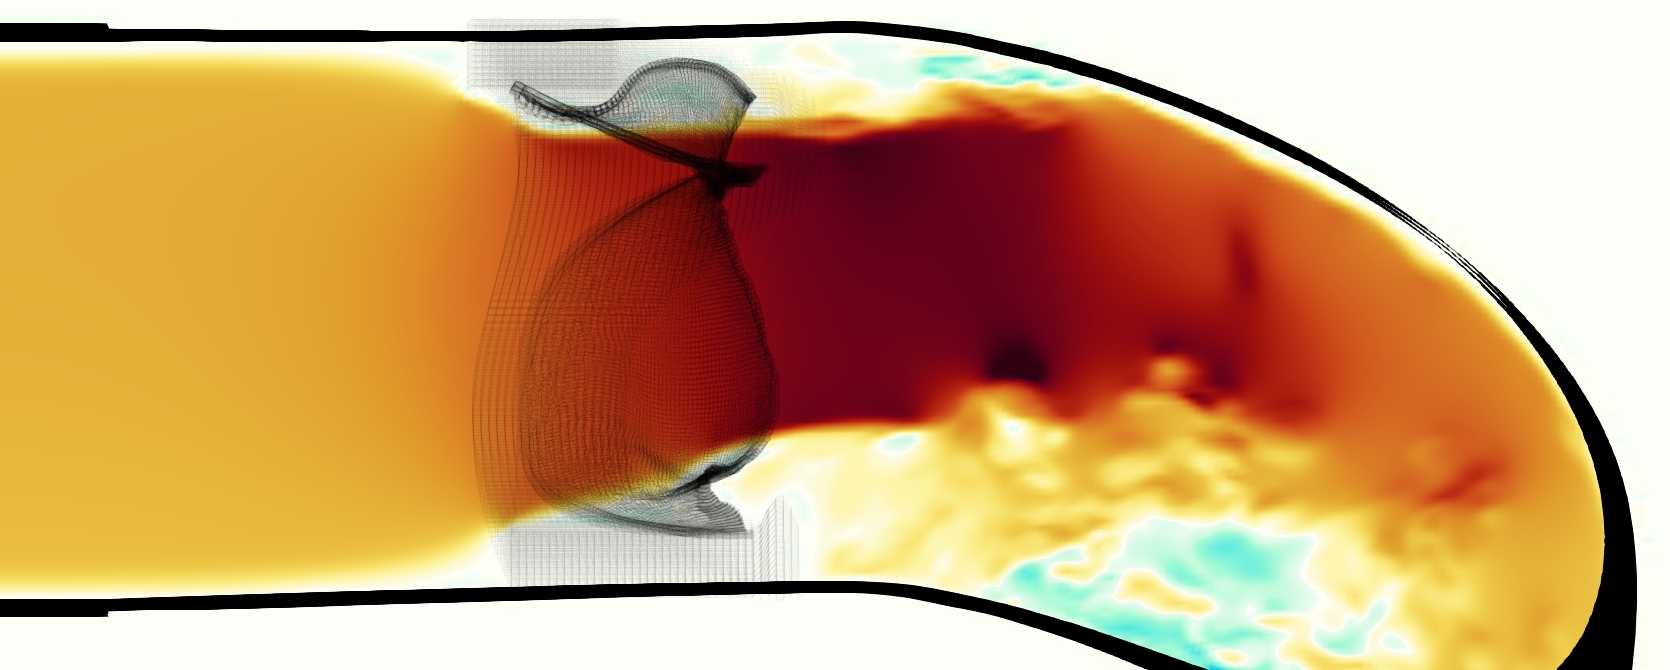

The emergent hemodynamics showed excellent qualitative agreement with experiments. Slice views of the axial component of fluid velocity ( component) in the sagittal plane that cuts through the center of the vessel, parallel to the flow direction, are shown in Figure 5. The flow in both the simulation and the experiment began to accelerate at the same time, with a jet forming through the open valve leaflets. The velocity, angle, and shape of the jet agreed well between the two cases during systole. The simulation captured the slight upward angle of the jet, which was not fully centered in the vessel. It also matched the location where the jet impacts the wall and the slower speed of the jet as it turns with the MPA downstream. As the flow decelerated, the fluid along the interior curve of the vessel reversed first while forward flow persisted where the jet was strongest, as seen in both the simulation and experimental results.

In both the experiment and the simulation, a separation region of reverse flow developed along the interior curve of the vessel under the core jet through the valve. The reverse flow began to develop at the same time in the cardiac cycle and grows throughout systole. The simulation lacked reversed flow in the entire region where reversed flow was present in the experiment, but this region developed some flow separation and had much slower flow than elsewhere in the vessel. Thus, the simulation captured that this is a distinct region from the core jet through the valve opening. There was a smaller amount of slower and slightly reversed flow along the outer curve of the vessel, close to the valve annulus and scaffold support. This region was well-matched between the experiment and the simulation.

Slice views of the (axial) component of fluid velocity in the axial plane, orthogonal to the flow direction, show that the simulation replicated the development of the jet over the cardiac cycle. At each phase, the simulation matched the forward speed of the core of the jet and the locations of reverse flow back towards the valve annulus. While there are some differences in the shape of the jet at certain phases and locations, the simulation clearly produced the general dynamics of the cardiac cycle that are seen in the experiment.

A comparison between the phase-averaged velocity resampled onto the MRI grid, the phase-averaged velocity without resampling, the instantaneous flow field without resampling and the MRI velocity field is shown in Figure 8. The coarser resolution is visible as a “stair-stepping” or “pixelated” effect on the phase-averaged resampled velocity, whereas the edges of the jet are more smooth in the phase-averaged velocity with no resampling. Otherwise, the resampled velocity appears qualitatively similar to the phase-averaged velocity with no resampling. Fine scale features were present in the instantaneous field that were lost in the phase-averaging and resampling process. There was more variation in the local velocity of the center of the jet and local areas of high velocity at the edges of the jet that suggested vortices. Vortical structures adjacent to the jet and in the areas of reversed flow were apparent. These comparisons suggest that 4D flow MRI data may lose substantial fine-scale flow features in the flow field via phase-averaging.